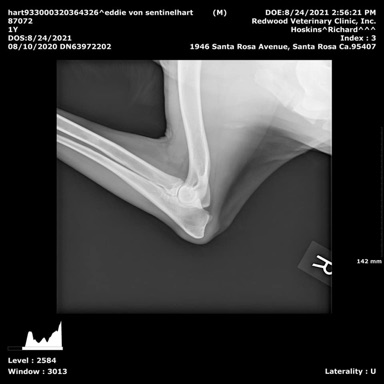

SV Hips A1

SV Elbows  Normal